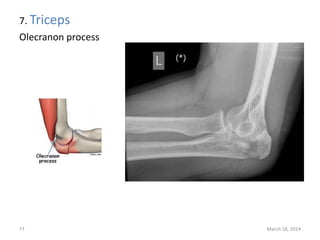

The document lists 10 common sites of avulsion fractures caused by the tearing away of tendons or ligaments from bone. It identifies the specific muscles or tendons that can cause avulsion fractures at the iliac crest, ischial tuberosity, greater trochanter, lesser trochanter, posterior calcaneus, olecranon process, superior patella, inferior patella, and tibial tuberosity.